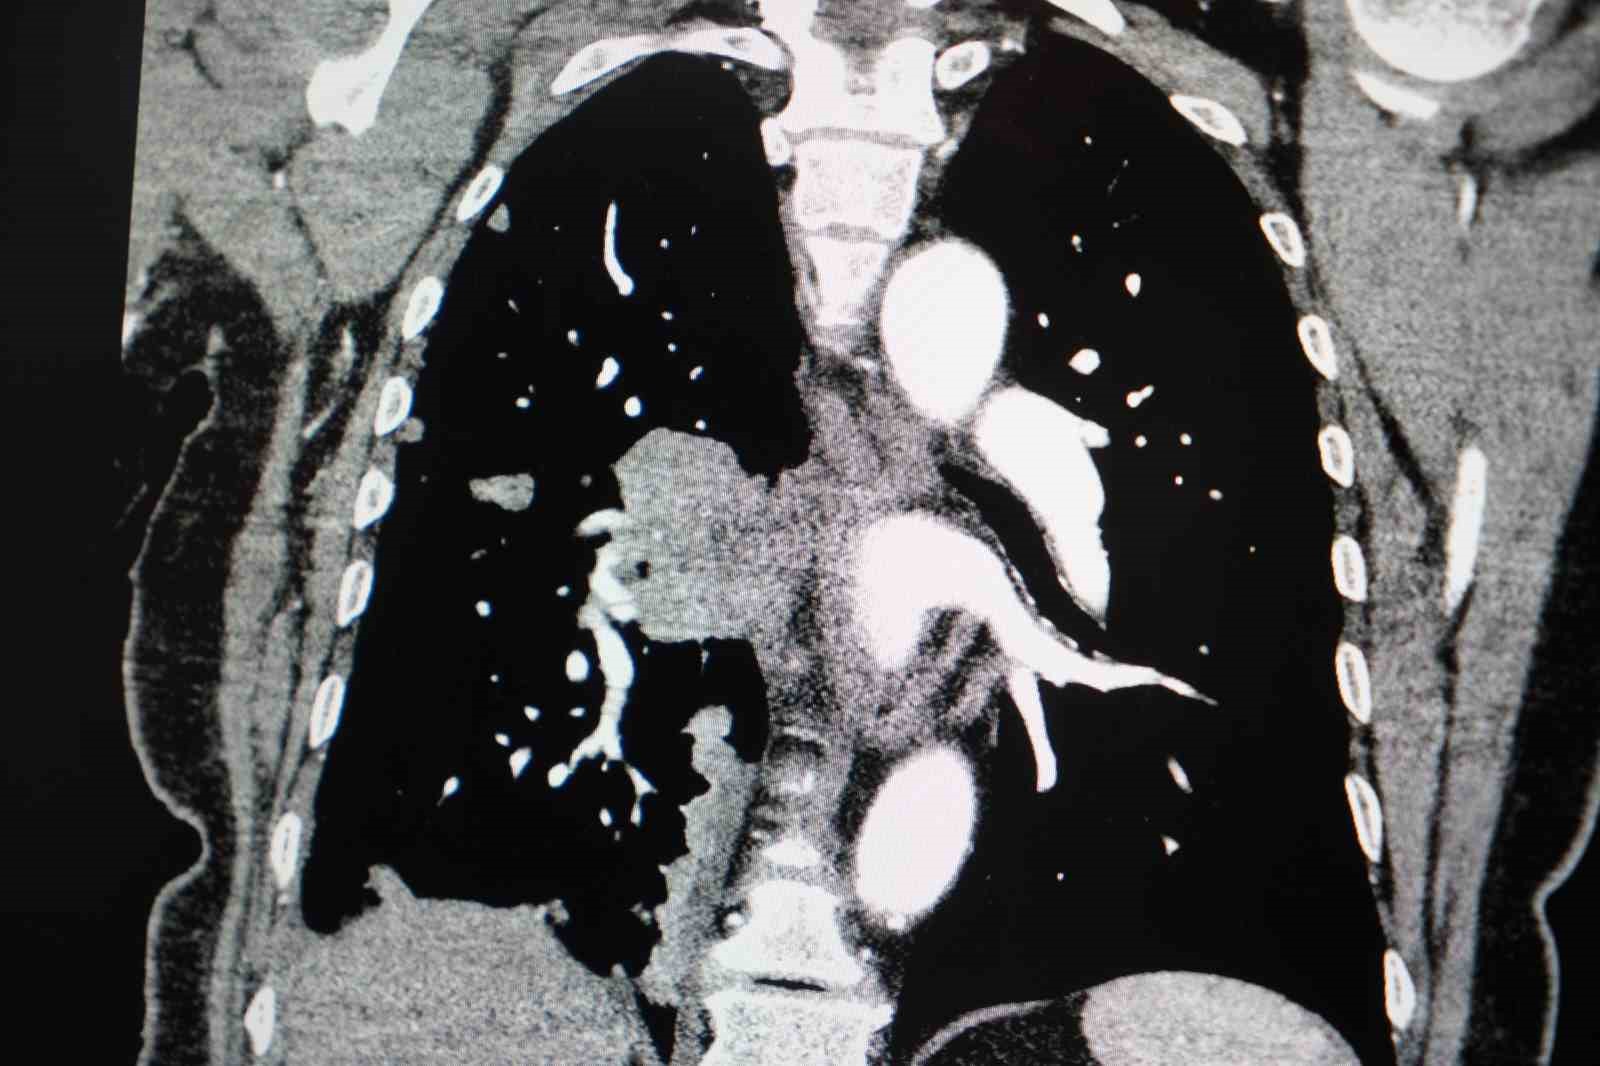

Akciğer kanseri vakalarındaki artışa da dikkat çeken Özkaya, "Son yıllarda hem sigara içen hem de hiç sigara kullanmamış bireylerde akciğer kanseri vakalarında dikkat çekici bir artış görüyoruz. Özellikle kadınlarda adenokarsinom tipi akciğer kanseri belirgin şekilde artış göstermektedir., Yapılan son araştırmalara göre akciğer kanseri teşhislerinin yaklaşık yüzde 20’si hiç sigara içmemiş bireylerde konuluyor. Bunun en önemli nedeni pasif içiciliktir. Yani siz sigara içmeseniz bile, yakın çevrenizde sigara içiliyorsa akciğer kanseri riskiyle karşı karşıya kalabilirsiniz" ifadelerini kullandı.